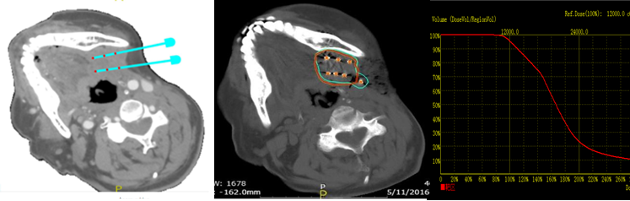

圖1 3D打印模板粒子植入手術(圖A為3D打印模板制作;圖B術中植入;圖C、D為術前計劃及術后驗證;圖E為術后即刻劑量體積直方圖。)